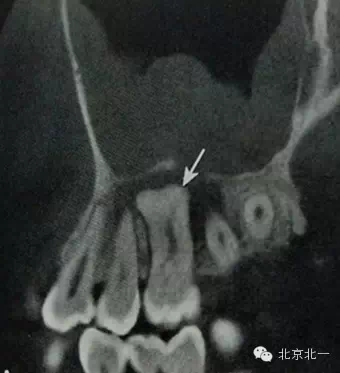

【CBCT表現(xiàn)】:

在CBCT上,根尖型骨島無低密度帶狀影包繞,與周圍骨質(zhì)分界清晰,具有特征性的毛刷樣邊緣,且其發(fā)生區(qū)域的牙根牙周膜影像連續(xù)、完整、不導(dǎo)致頜骨的膨隆。

右下頜C4根尖區(qū)課件一類圓形高密度影,與周圍骨質(zhì)分界清晰,C4牙周膜影像連續(xù)、完整,下頜骨未見膨隆。